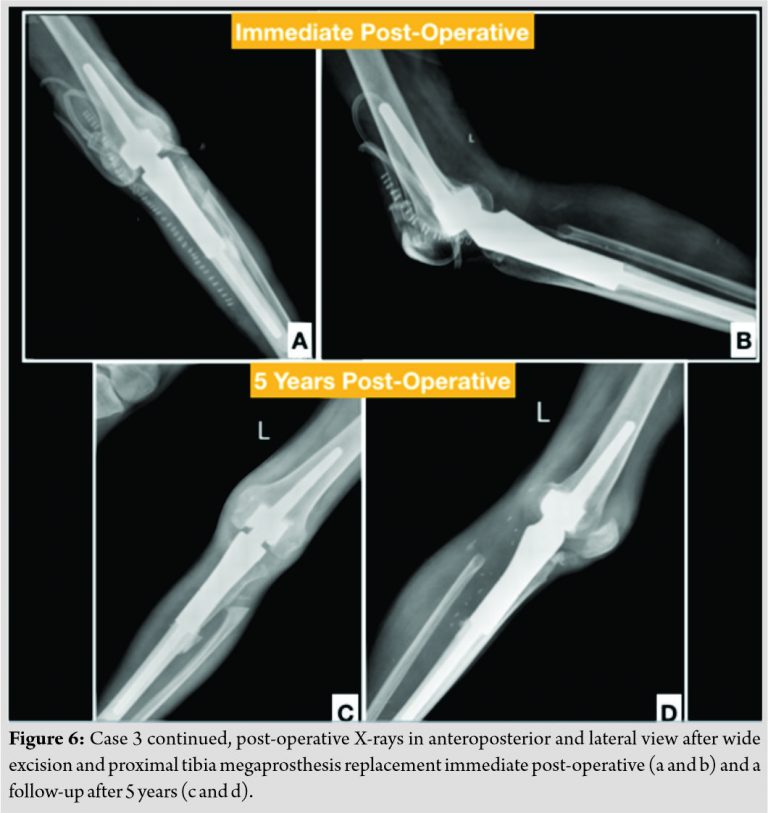

A 31-year-old male presented to the hospital with slow-growing swelling in the left proximal tibia for 7–8 years. The patient gave a history of fall 1–2 months before presentation and was unable to bear weight on the affected limb. On examination, a large mass was palpable arising from the proximal tibia extending posteriorly, laterally, and superiorly across the knee joint. Popliteal pulsation could not be felt, but dorsalis pedis was palpable and the patient had no neurological deficit. The patient had a fixed flexion deformity of 60° with no further range of motion possible at the knee joint. The X-ray showed large calcific lesion arising from the upper end of tibia and likely from fibula (Fig. 5a and b). The calcification was chunky and irregular in nature and appeared to be a secondary sarcomatous change in a case of long existing osteochondroma. The MRI suggested of an irregular osteochondromatous lesion extending toward the posterior neuromuscular bundle but not invading it (Fig. 5c and d). All pre-operative investigations were normal and a decision was taken to widely resect this tumor and implant a proximal tibia replacement megaprosthesis to allow limb salvage. A gross 13 cm long proximal tibial segment was resected and sent for intraoperative histological analysis. The tumor was lobulated with a cartilaginous cap and measured 10 cm×9cm×6 cm (Fig. 5e and f).

The tumor had eroded the posterior cortical margins. Also resected was a 4cm stump of proximal fibula which showed involvement intraoperatively. The histopathology revealed irregular mass of bony trabeculae with island of hyaline cartilage with extensive enchondral ossification. The newly ossified bone showed characteristic blue coloration in the intratrabecular space with no atypical cellular proliferation, thus confirming the diagnosis of BPOP. On regular post-operative follow-up, the patient recovered good quadriceps and hamstrings strength with knee range also recovering between 0 and 90°. No signs of recurrence were seen on a 7-year follow-up (Fig. 6.)